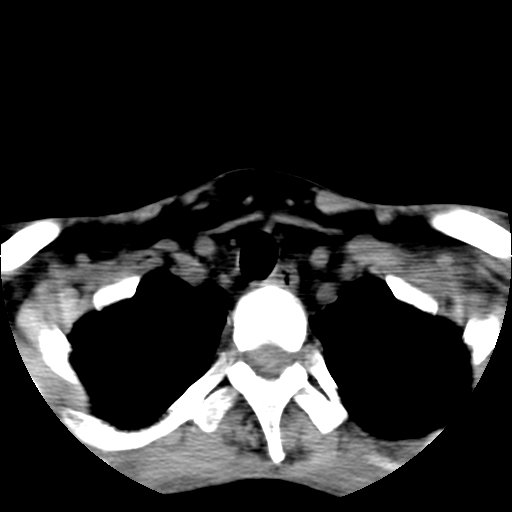

标题: CT24019:男,45岁,发现颈部肿物5个月。 [打印本页]

男,45岁,发现颈部肿物5个月,彩超示:双侧颈部及下颌部软组织增厚。

考虑双侧颈项部良性对称性脂肪增多症。